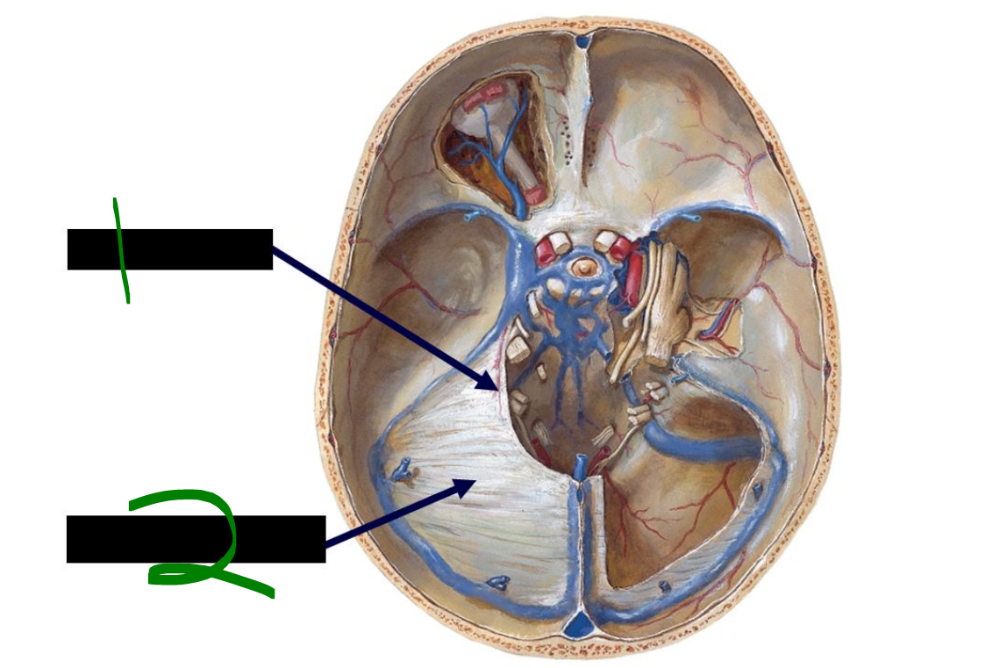

card image

What is 7?

primary auditory cortex

49

What is 8?

temporal lobe

50

What is 9?

sylvian fissure

51

What is 10?

frontal lobe

52

The primary motor cortex is located in the ______ ______ and corresponds to Brodmann's area ______.